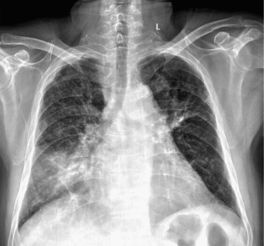

干燥综合征的核心病理在于免疫系统功能紊乱,错误地将人体自身的泪腺、唾液腺等外分泌腺体当作攻击目标,导致腺体被破坏、分泌功能严重下降。患者所经历的“干”,远非饮水所能缓解。典型的口干,严重时可能导致吞咽干性食物(如馒头)必须借助水送服,长期甚至引发猖獗性龋齿,牙齿呈片状剥落。眼干则表现为持续的眼干涩、异物感、少泪或无泪,痛哭时亦无泪水,严重者可导致角膜损伤甚至溃疡。其危害远不止于口眼。当免疫风暴蔓延至腺体外,可累及皮肤、关节、肺、肾、肝、消化道、血液系统乃至神经系统,引发诸如皮肤紫癜样皮疹、关节疼痛、干咳、肺纤维化、肾小管酸中毒、消化不良、血细胞减少等多种复杂并发症。正因如此,干燥综合征绝非简单的“缺水”或“上火”,而是一个需要系统性管理的全身性疾病。